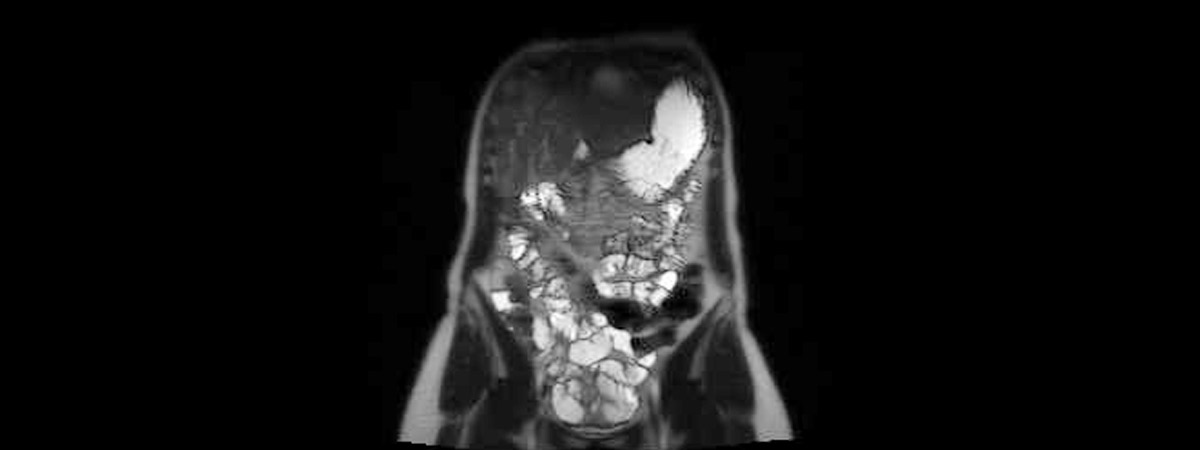

Häufige Fragen betreffen Erkrankungen der Leber, der Gallenwege, der Bauchspeicheldrüse und der Nieren und Nebennieren. In MRT können neben gutartigen Erkrankungen (z.B. entzündliche Veränderungen, Steinerkrankungen, angeborene Fehlbildungen) auch Tumore dieser Organe erkannt werden.